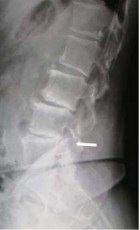

由於退化性脊椎炎容易造成局部血液循環之下降,常於長時休息一段時間後,有下背酸痛的現象,尤其年長者在清晨或久坐後症狀較為明顯,但經過短時間之活動後症狀即逐漸減輕或消除 (Teraguchi, 2014:104-110; Peng, 2006:583-587)。(參見圖 2)

圖 2 第四五腰椎退化(如箭頭所示)